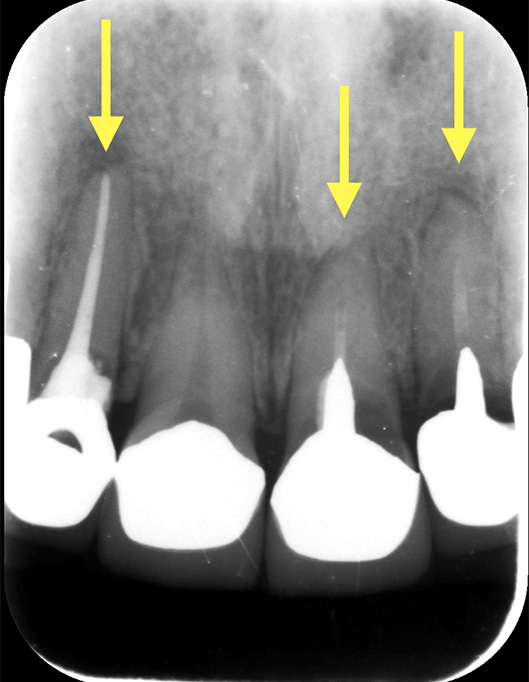

根管治療が必要な歯は大きく分けて2つあります(この2つ以外にもありますが、割合は低いため割愛させていただきます)。ちなみに過去に根管治療した歯は、レントゲンを撮ってみると、見分けることができます。(図1)

歯の根管の中に白い材料が入り込んでいるのが分かる